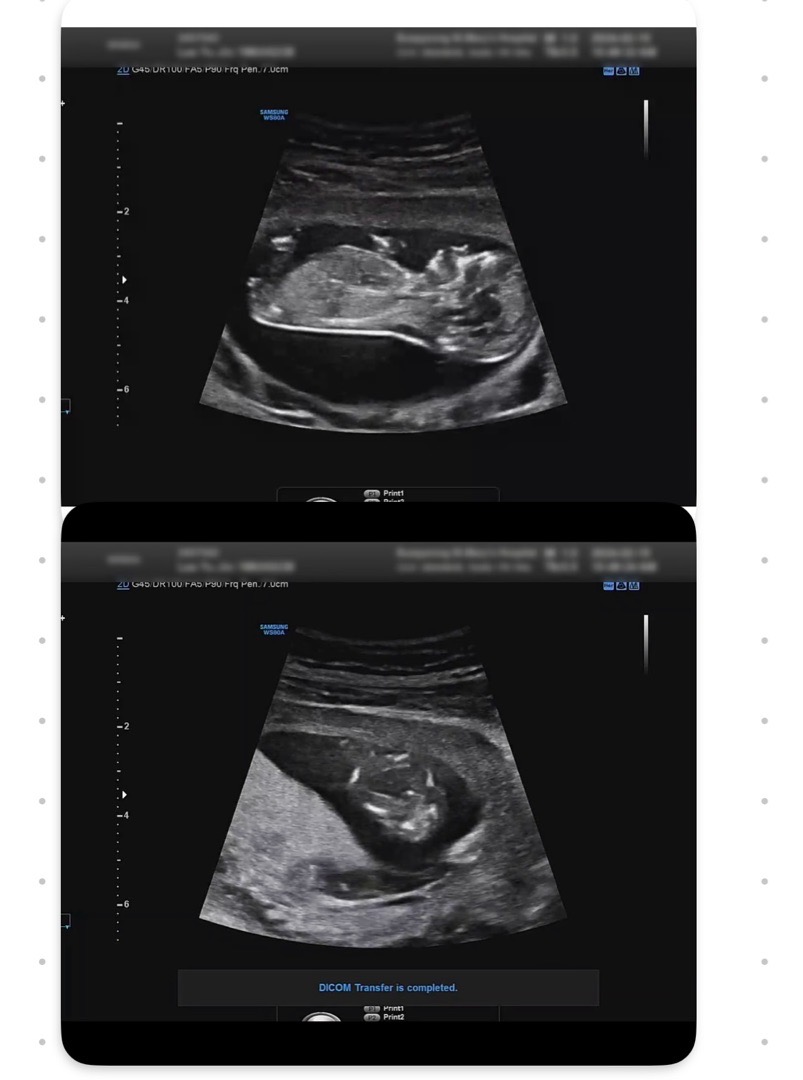

아들인거 같은데 맞을까요?!

각도법 고수님 계시면 부탁드립니다ㅠㅠ 12주 0일 이구요! 다리사이에 뭐가 보이긴 하는데 쌤은 아직 남자나 여자나 둘 다 보일 시기라고 모르겠다고 하시네요ㅠㅠ 어떻게들 보이실까요?!

생식기 갈라지면 보통 딸이라고 하시던데 딸같아요

다리사이에 살짝튀어나온게 아들같아용

딸은 아무것도 안보이는데 아직은 너무 일르긴하네용